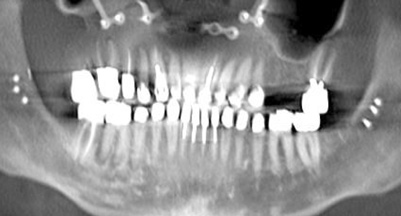

Fig 6. Panoramic radiograph of 56-year-old patient illustrating a number of dental procedures historically.

Figure 6

Fig 7. Existing dentition was sound periodontally and reasonably esthetic.

Figure 7